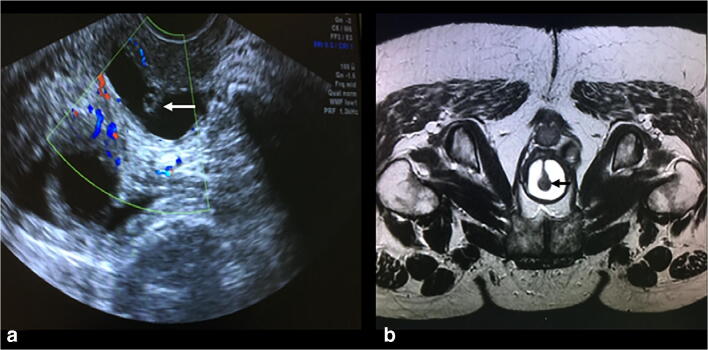

Fig. 2.

a Transvaginal ultrasound showing the urethra surrounded by the diverticulum. b MRI showing the same part of the urethra. The arrows demonstrate the urethra suspended within the diverticulum